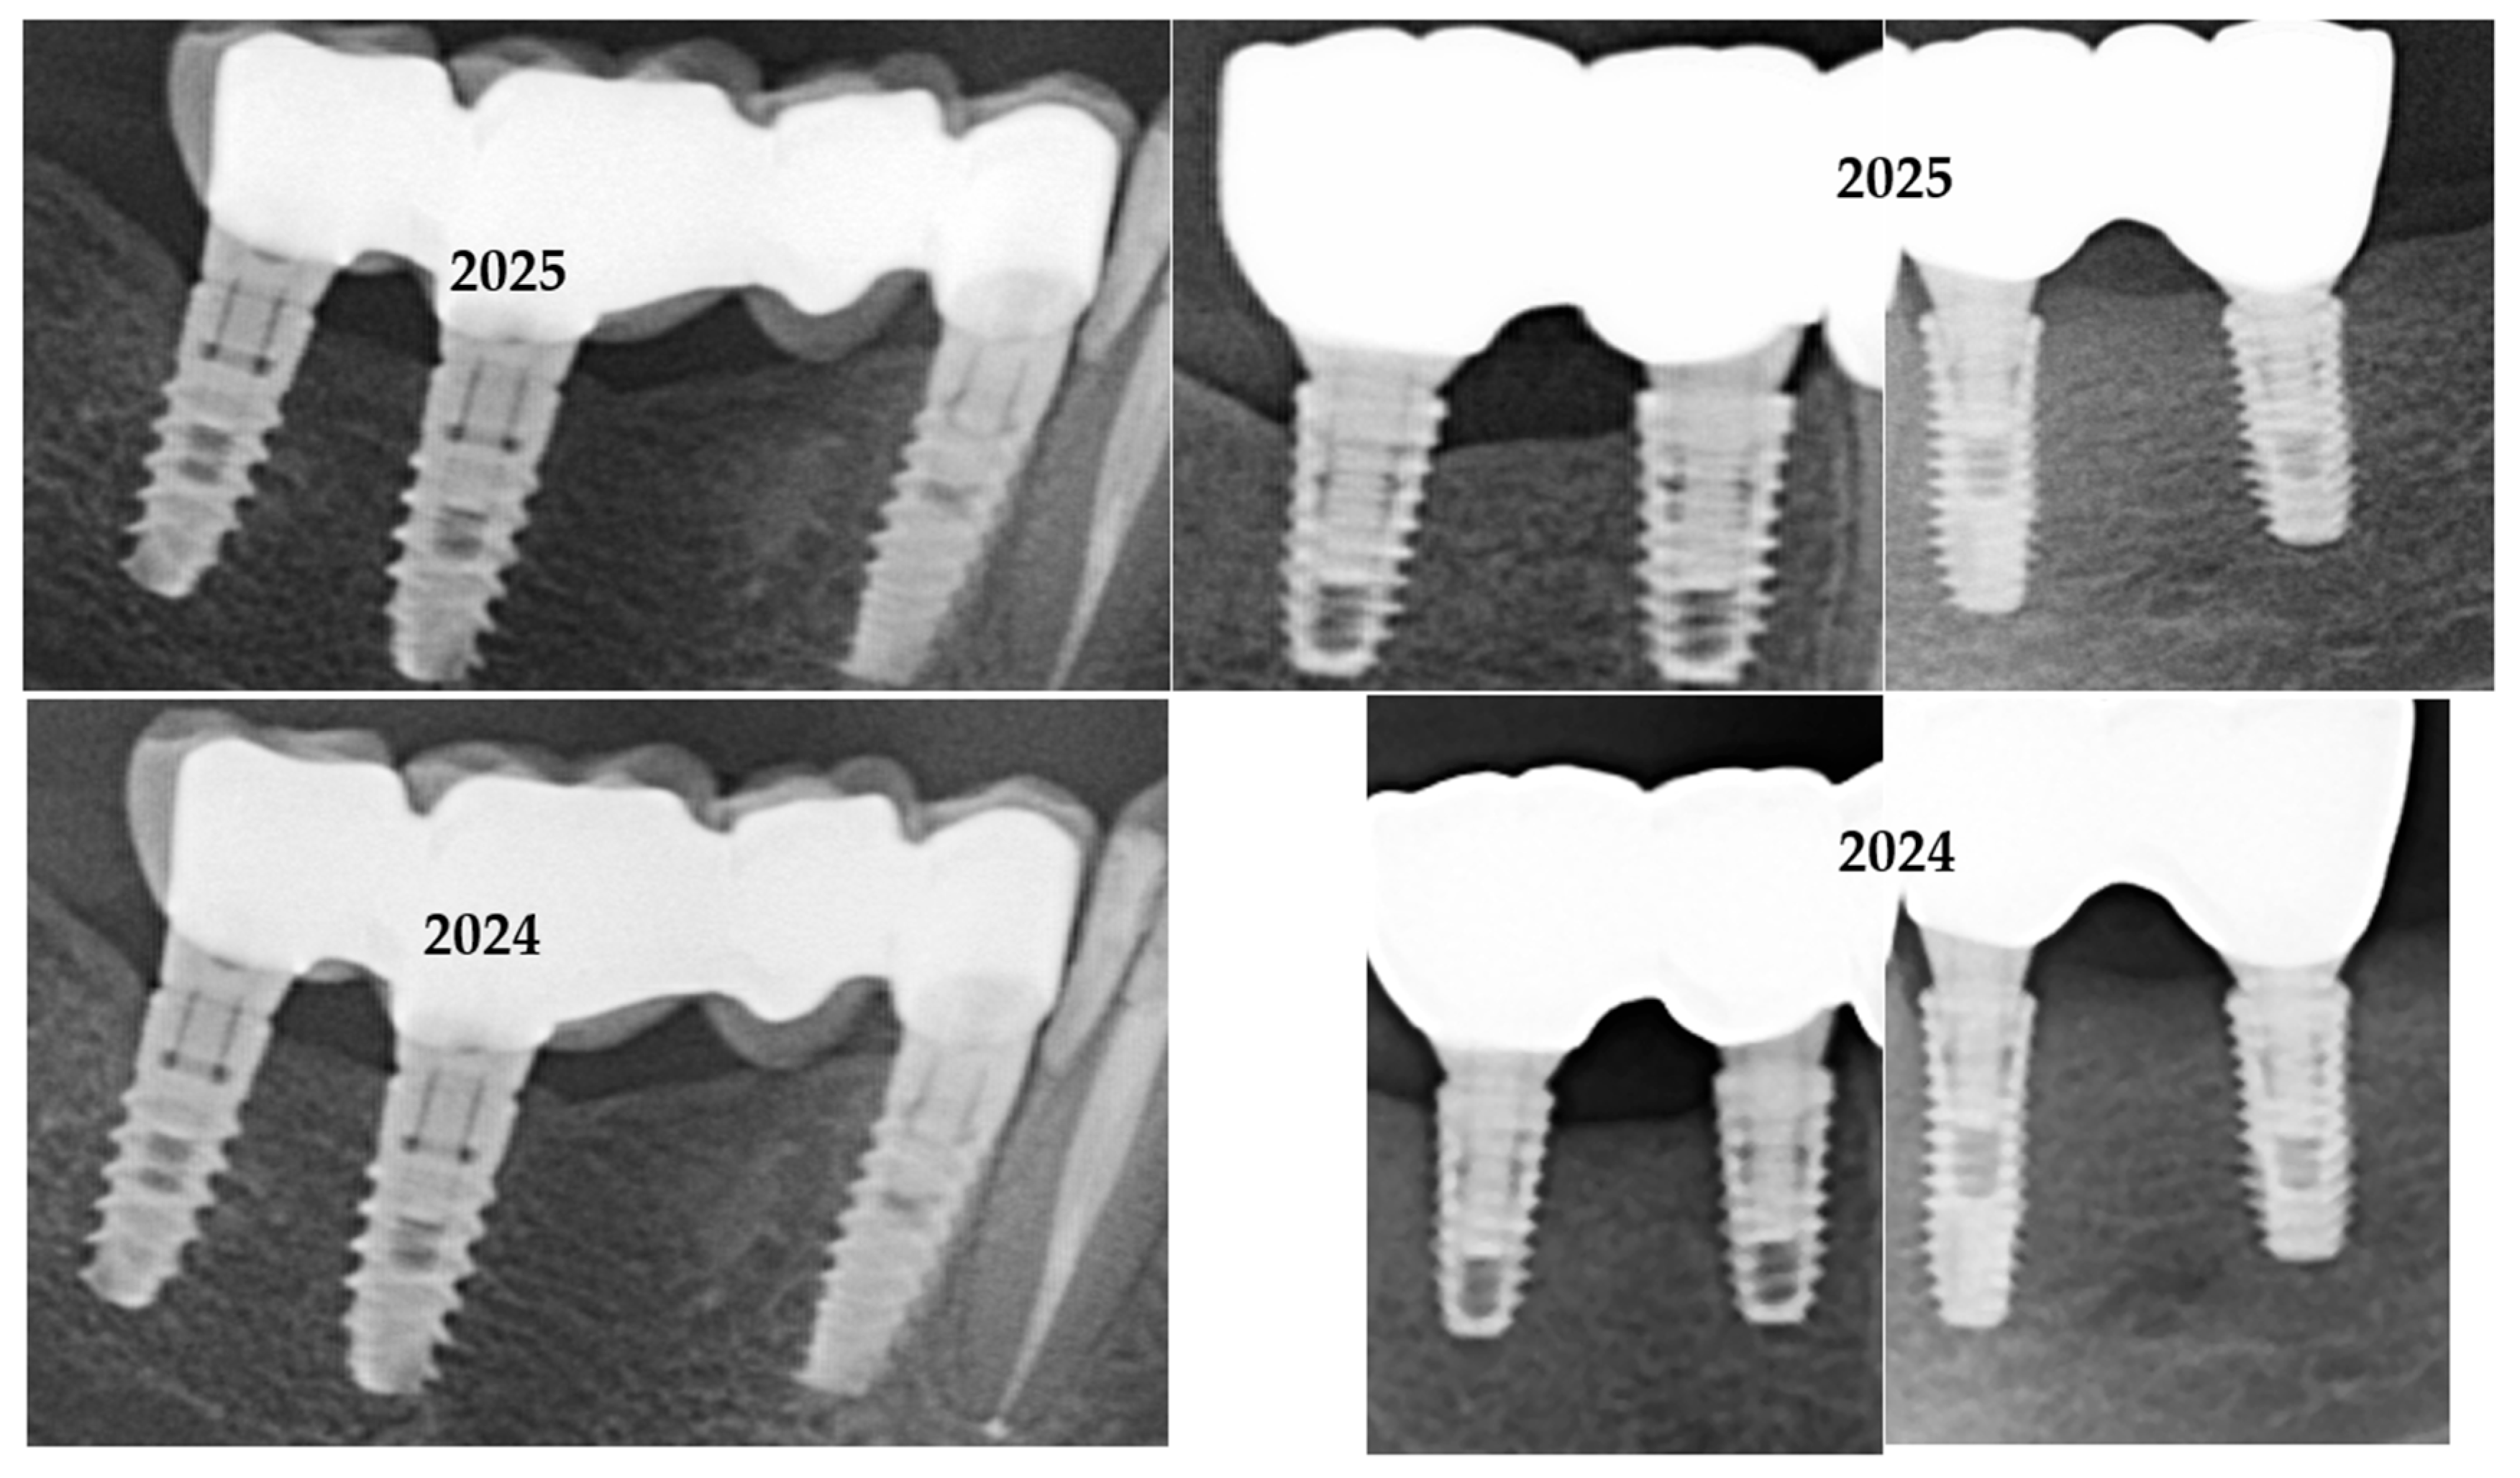

3.4. Marginal Adaptation Evaluation

Marginal adaptation was initially assessed for all cases using conventional two-dimensional (2D) periapical and panoramic radiographs (Figure 7). Due to the intrinsic resolution limitations of these imaging modalities—approximately 150 μm for panoramic imaging and 75 μm for CBCT scans—precise quantitative measurements of marginal gaps could not be reliably performed using radiographs alone. No gross misfits, open margins, or overhanging contours were detected in any of the reviewed images, and all restorations were classified as radiographically acceptable, without apparent marginal discrepancies linked to early failure or peri-implant inflammation.

To supplement the radiographic evaluation, a subset of clinical images was analyzed using ImageJ software (Fiji version) to obtain semi-quantitative estimates of marginal gaps. Radiographic images were imported into ImageJ (NIH, Bethesda, MD, USA) for marginal-gap evaluation. Each image was calibrated to real dimensions using a visible reference, such as the known abutment diameter. The pixel-to-mm scale was set in ImageJ using this known reference dimension visible in each image. For each restoration, three points were selected along the visible crown–abutment interface within the 2D radiographic projection (typically near the mesial, central, and distal regions of the imaged side). Linear measurements were taken perpendicular to the interface at these locations to estimate the apparent gap width. Each time, three measurements were performed, and mean values were calculated after verifying consistency. The results were interpreted as qualitative indicators of marginal adaptation, suitable for comparative analysis between groups rather than absolute measurements. These ImageJ-derived values were interpreted strictly as semi-quantitative approximations, not true marginal-gap measurements, due to the intrinsic resolution limitations of 2D radiography.

Although these measurements were constrained by image resolution and calibration, they suggested a trend toward smaller marginal discrepancies in restorations cemented with Fuji Plus® compared to those cemented with DentoTemp™. Representative radiographic examples from the study are presented in Figure 8.

Figure 8. Sections of OPGs from study cases. The left panels (a,c,e,g) show restorations cemented with Fuji Plus®, while the right panels (b,d,f,h) show restorations cemented with DentoTemp™. Images illustrate representative follow-up cases used for radiographic evaluation of retention and marginal adaptation.